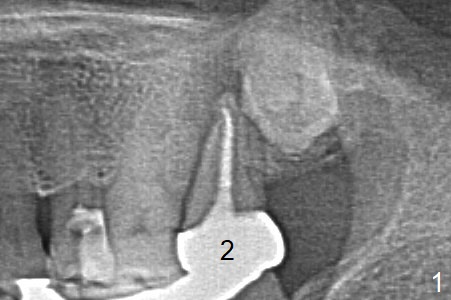

Osteotomy in Mesial Slope A 64-year-old woman will return for extraction/implant for the upper left 2nd molar with a fistula (Fig.1). Since the roots deviate distal (Fig.2 after extraction), initiate osteotomy in the apical 1/3 of the mesial slope with 1.5 mm drill (Fig.3). Once the lamina dura is penetrated, change trajectory (Fig.4) and extend depth for 15 mm (gingival level). After use of 2 mm drill, insert marked parallel pin for PA. The final implant as well as abutment is shown in Fig.5. Return to